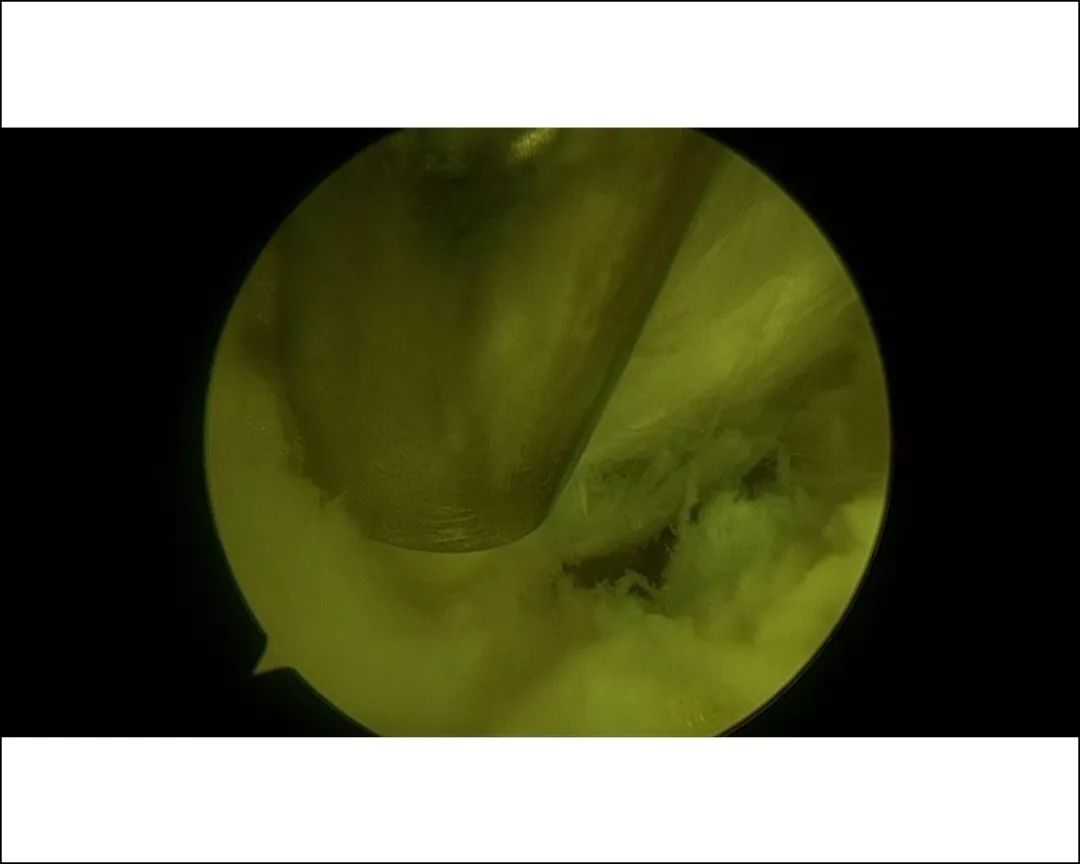

骨伤二科主任医师方磊经过与治疗团队认真讨论后,为患者制定了全新的微创手术方案,行关节镜下跟骨骨刺摘除术,手术取足跟部内侧两个0.5cm长小切口,在关节镜监视下切除增生骨赘,清理修整骨刺周围炎性组织,同时行跖筋膜松解,成功完成手术,目前患者术后恢复良好。

视频加载中...